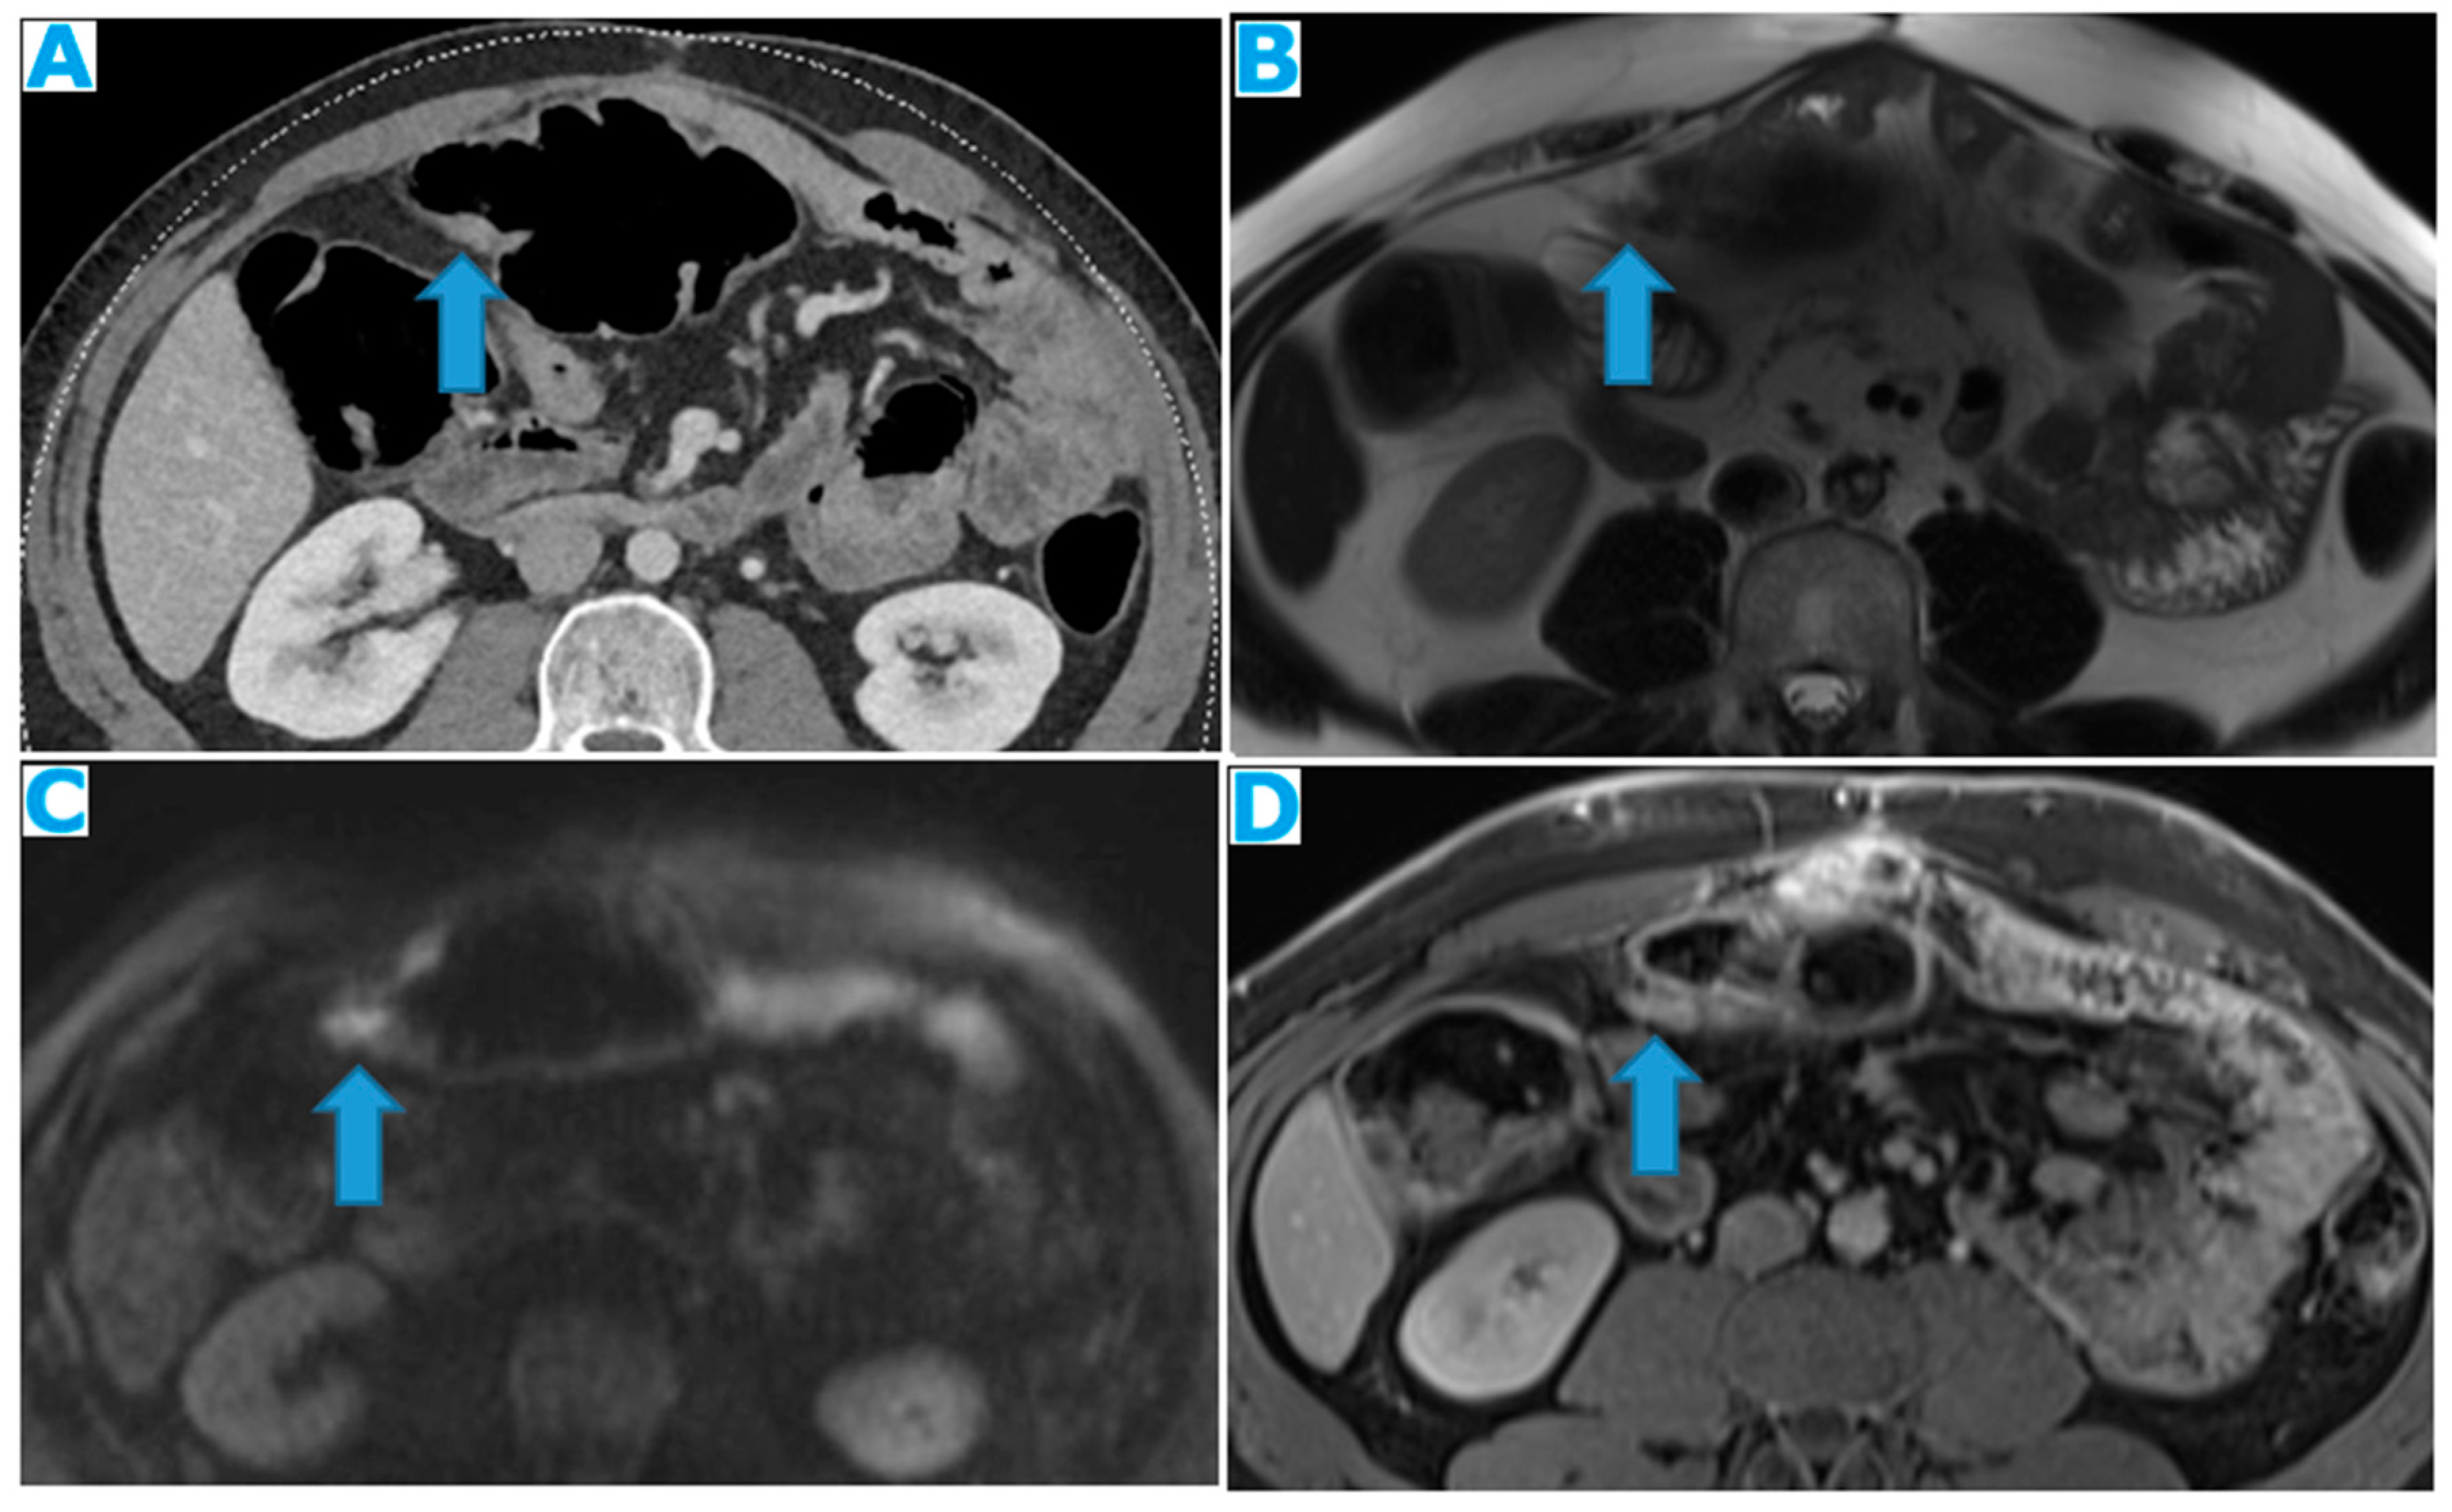

Figure 22.

Axial T2WI (A), axial DWI (B), CE portal phase FST1WI (C). PC from duodenal adenocarcinoma: Deposit within the distal ileum serosa. Axial CE-CT (D). PC from breast carcinoma: Deposits within the caecal serosa.